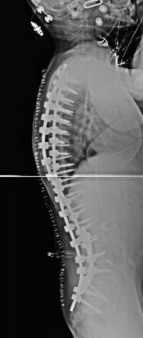

Qui di seguito, un esempio di un paziente affetto da scoliosi severissima, sottoposto a trattamento chirurgico.

Prima dell’intervento: